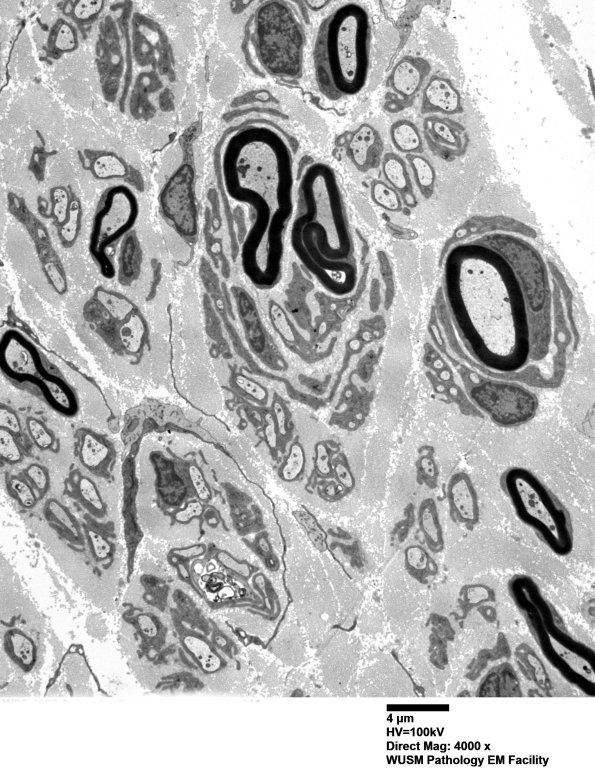

Pseudo-Onion bulbs frequently are composed of non-contiguous sectors of Schwann cell processes. (electron micrograph)